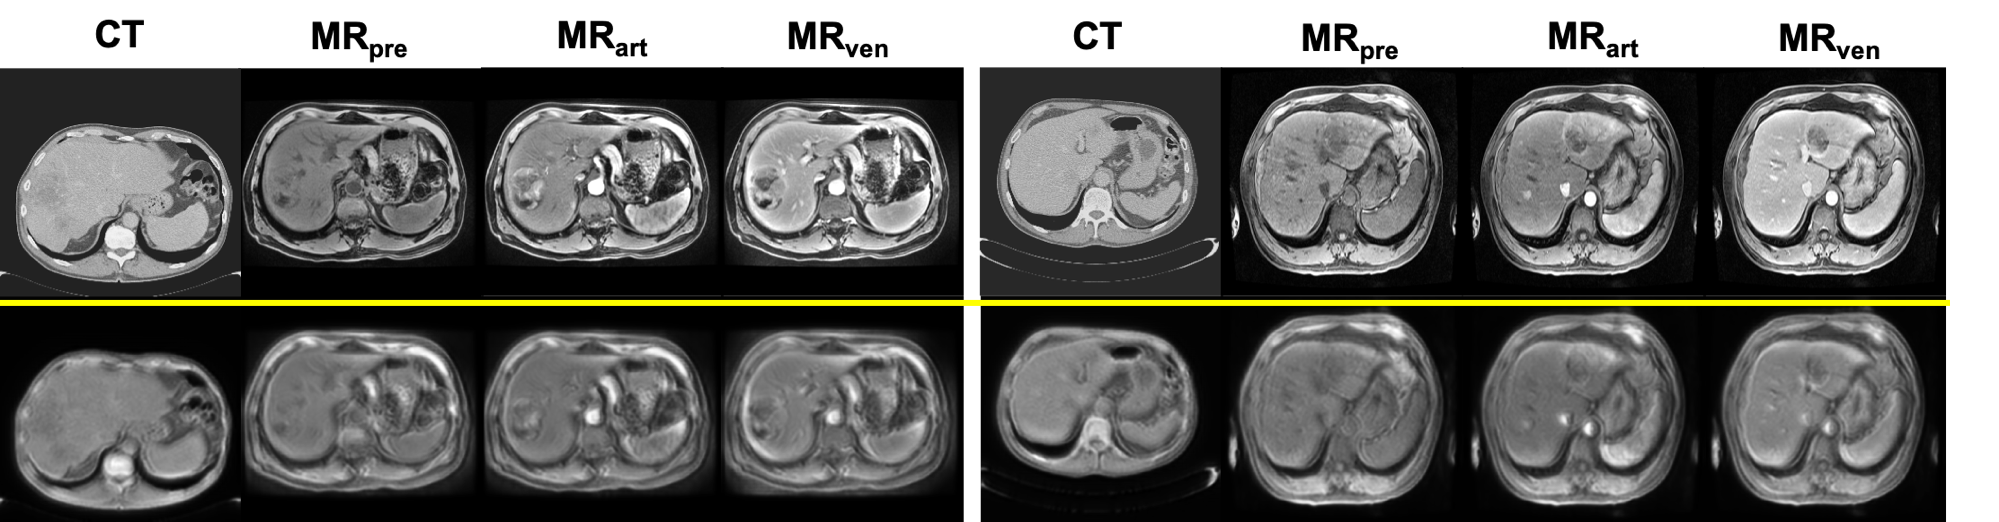

Figure 3: Two examples of style transfer with CycleGAN, Left to right: CT, generated MR, MR

[Uncaptioned image]

Figure 4: Two examples of content-only images via disentangled representations, Left to right: CT, content-only CT, content-only MR, MR

For comparison purposes, we trained a CycleGAN model with unpaired CT and pre-contrast MR images and performed style transfer on test CT images to generate synthetic MR images. A standard UNet was trained on synthetic MR images and validated on real precontrast MR images. It achieved a DSC score of 0.72 (see Table  1) with subject-wise 5-fold cross-validation. Fig.  3 shows two examples of synthetic MR generated by CycleGAN.

Our DRLModule embeds cross-domain images into a shared content space and generates content-only images. Fig.  4 shows two examples of content-only images via Disentanglement Representations. We trained the UNet model on content-only CT and validated on content-only MR with 5-fold cross-validation and achieved a DSC score of 0.81 (see Table  1).